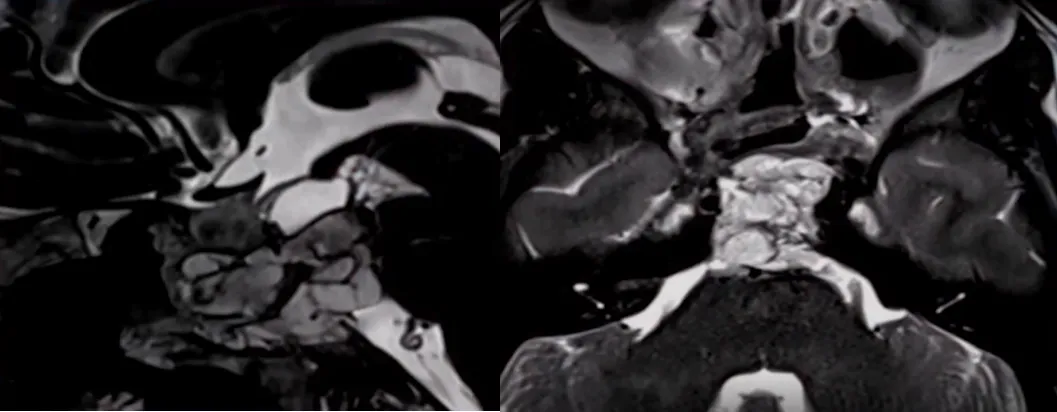

这是一个非常具有挑战性的脊索瘤,因为它渗入了基底动脉的血管壁,以及基底动脉的大部分分支。肿瘤纤维化程度很高,正如磁共振弥散成像显示的。基底动脉是位于脑干腹侧的一条重要血管,由左右两条椎动脉在颅腔内汇合形成,向上延伸并分出大脑后动脉等分支,主要负责为脑干、小脑、丘脑及部分大脑输送血液和氧气,是维持生命中枢功能的关键血管。

基底膜完全被肿瘤包裹和阻挡,因此福教授术中花了很长时间才把这些分支从肿瘤中分离出来。

在这里,福教授使用了“筷子技术”,在狭窄的通道里,可以有足够精准的操作来做到这一点。在这种情况下,福教授只使用了一块脂肪来完成闭合,填塞脂肪后,患者术后可以很快就坐起来。福教授认为其中一个诀窍就是在手术后让病人尽可能快地保持直立的姿势,以降低颅内压。

借助角度镜的广阔视野、成角器械的灵活操控,以及内镜医生那双极其灵巧而技术精湛的手,经鼻内镜手术正不断带来惊喜。